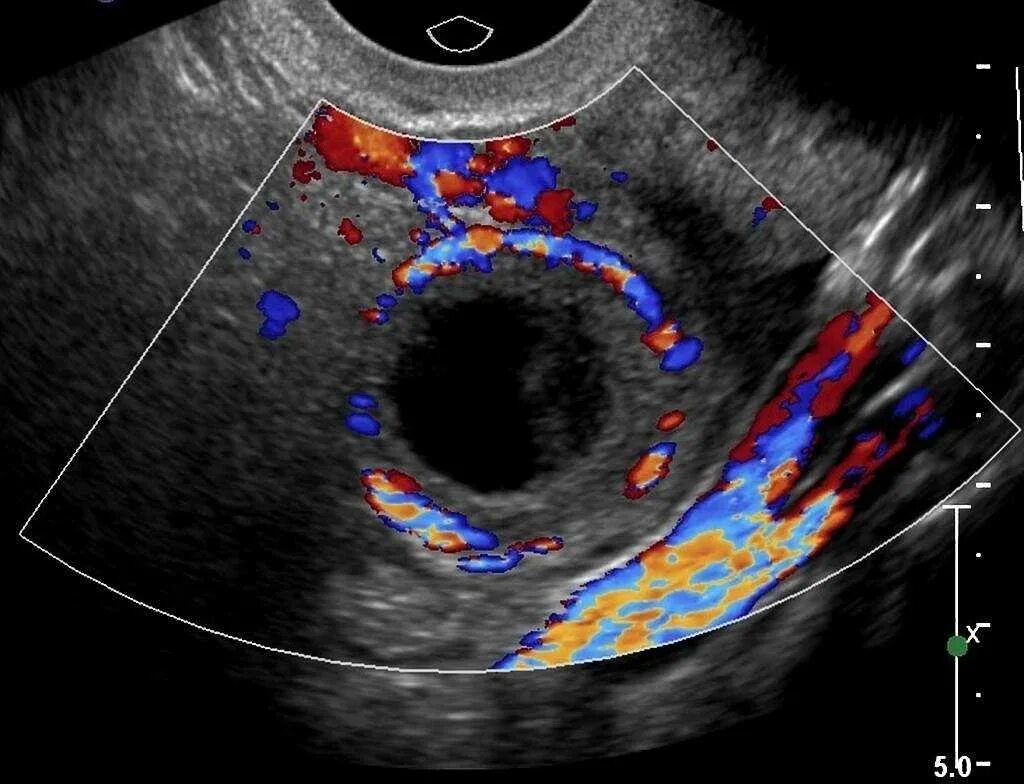

Образование анэхогенной структуры